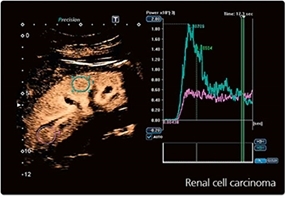

Изображения